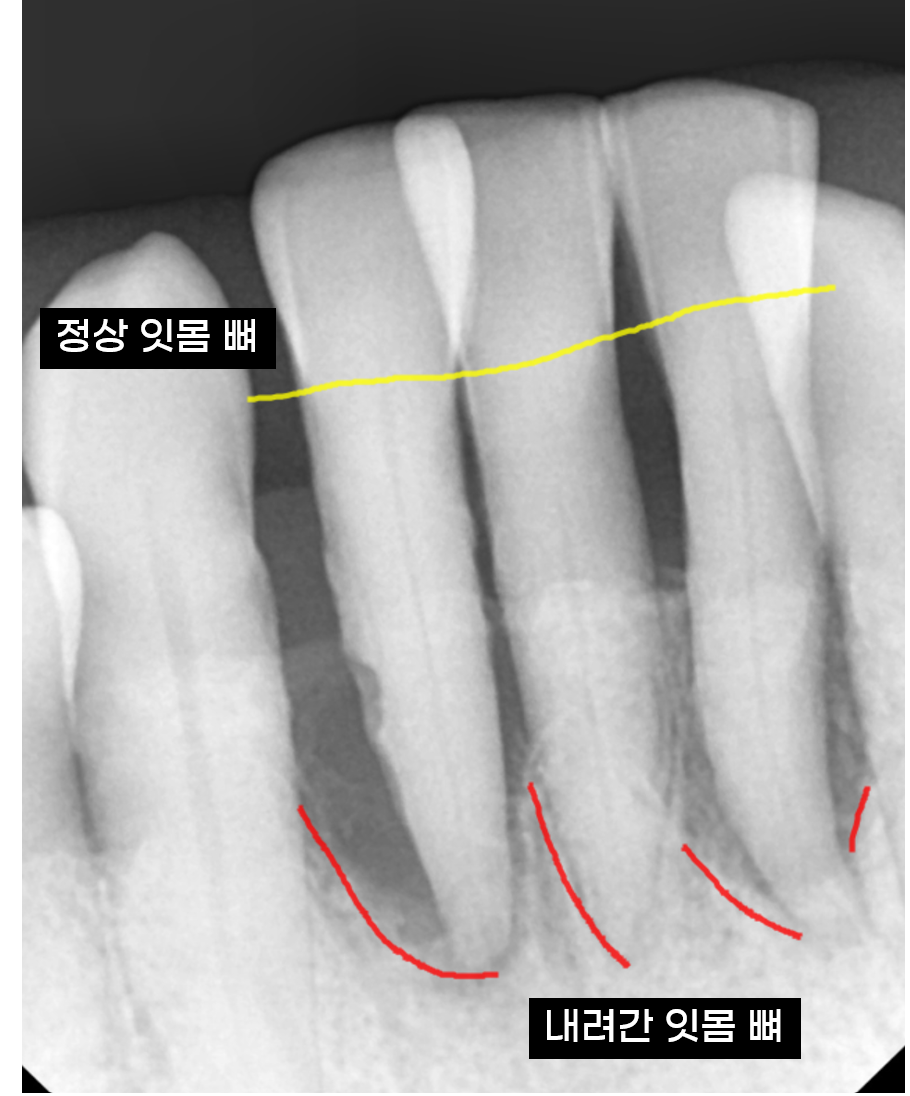

치아가 길어진 게 아니라,

잇몸뼈가 녹아내린 겁니다

치아가 길어보이는게 알고보면...

잇몸이 내려가면서 뿌리 부분까지 노출되어 길어져 보이는 것일뿐

실제 치아 길이가 길어진 것은 아닌데요.

240525

치주염이 진행되면 잇몸뼈가 점점 흡수됩니다.

염증이 뼈를 녹인거죠.

우리의 치아는 잇몸 뼈에 단단히 고정되어있는데

뼈가 치아 뿌리를 붙잡아주지 못하면,

뿌리 일부가 노출되며 치아가 길어진 것처럼 보이고,

결국에는 제자리를 이탈해 위로 솟구쳐 오릅니다.

240517 잇몸이 덮여져 있어야할 부분이 내려가기에 치아가 길어져 보이는 현상이 생겨요